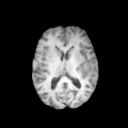

The results presented in Table 1 and 2 show our proposed method’s performance on unconditional 3D brain MR and chest CT image generation. Our proposed approach not only outperforms most comparing methods in FID and MS-SSIM metrics, it also has the lowest inference GPU memory footprint at a resolution of and was the only diffusion-based method that could be trained at a resolution of . Operating in the wavelet domain and profiting from the reduced spatial dimension also results in a relatively short inference time of / at the respective resolutions. Compared to the results presented in [23], we did not find that incorporating wavelet information into the network’s feature space (WavU-Net) increased the model’s performance. Qualitative results of our proposed method (WDM) are shown in Fig. 2 and 3. A qualitative comparison of samples produced by all evaluated methods can be found in the Supplementary Material.